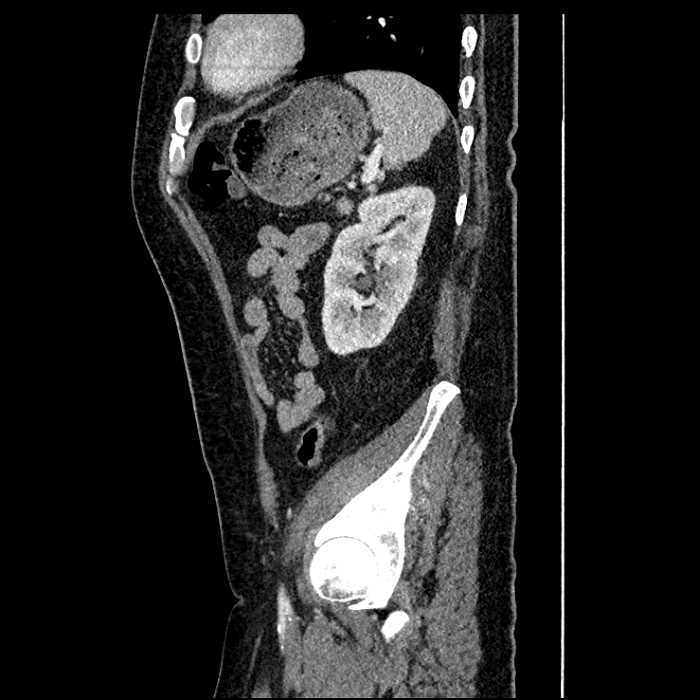

• Mild mural thickening of a segment of the sigmoid colon with adjacent fat stranding and a 1.5 cm fluid and gas collection along the tip of an inflamed diverticulum

• Loss of the normal fat plane between this collection and adjacent loops of small bowel, which demonstrate mural thickening

Acute sigmoid diverticulitis complicated by a small contained perforation and a large abscess in the right hepatic lobe. Additional small subcapsular abscesses along the anterior margin of the left hepatic lobe.

Additionally, loss of the normal fat plane between the peridiverticular collection and adjacent thickened loops of small bowel raises the potential for an enterocolonic fistula.

Hepatic abscess showing the double target sign with low density internally surrounded by a thin inner enhancing rim (red arrow) and ill-defined outer low density rim (yellow arrow). Blue arrow indicates an internal septation. Red arrows: additional smaller subcapsular abscesses. Red arrow: focal contained perforation associated with diverticulitis.